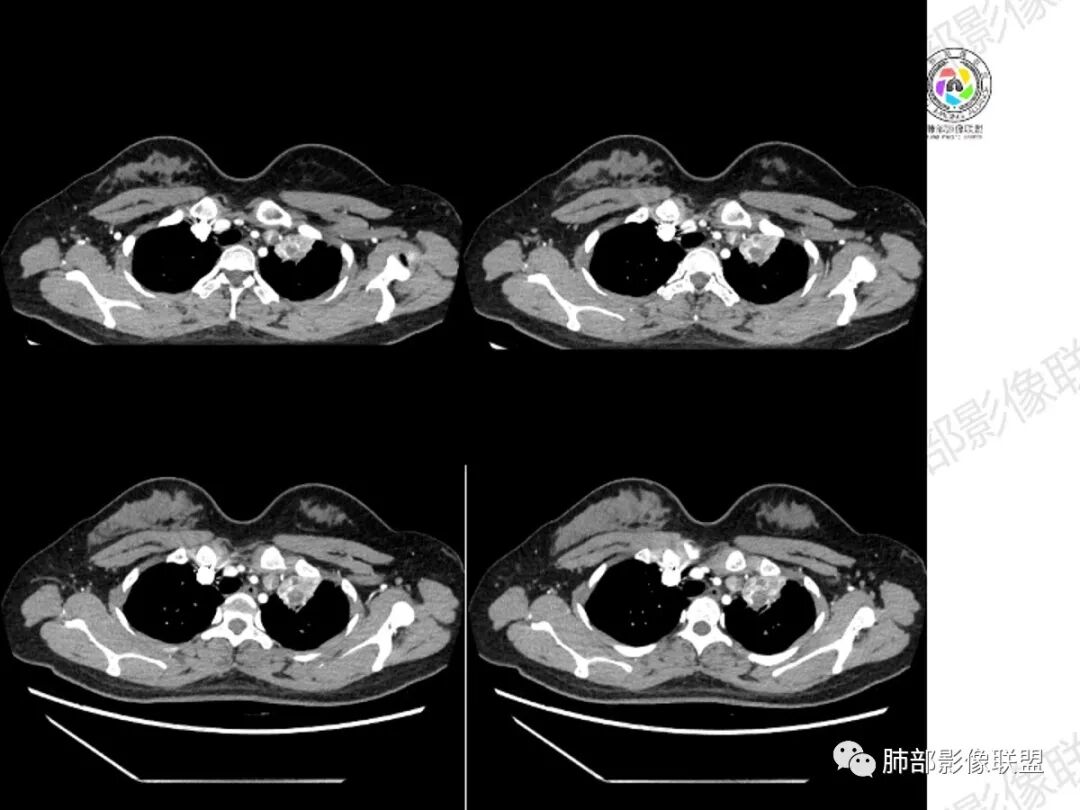

年轻女性,咳嗽咳痰一个月,左肺体积缩小,左肺尖部胸膜下实变影,宽基底与胸膜相贴,病灶边缘平直收缩,部分略膨隆,病灶下方可见支气管挤压,肺窗所示:周围伴有多发结节部分可见树丫征,纵隔窗可见病灶与纵隔胸膜黏连,部分与左肺动脉分界欠清,平扫密度尚均匀,增强扫描不均匀强化,内部可见多个低密度坏死,伴有条状血管影,纵隔淋巴结略有肿大。

年轻女性,慢性病程,左上叶纵隔旁大片实变,心脏纵隔左移,左主及左上叶支气管变窄呈针孔样,实变内可见斑点状钙化,显著不均匀强化,内可见低密度粘液拴,显著强化不支持TB,左上叶不张在腺癌少见,综合病变部位及强化表现考虑粘液表皮样癌,其次考虑类癌

年轻女性,咳嗦咳痰伴咳血1月多,ct可见纵隔左移,左肺容积减小,左肺上叶可见一不规则实变影,朝肺内侧边界清楚,部分边缘与纵隔界限模糊,临近支气管堵塞,内见点状钙化,增强不均匀强化,内可见多个低密度区,粘液?并与左肺动脉界限模糊,似受侵,考虑恶性,黏表?但病灶远端有多发小结节,卫星灶?结核待排

胸部CT:左肺体积缩小,左肺上叶前段纵隔旁胸膜下大片实变影,边缘清楚、匀齐、平直收缩,部分略膨隆,周围多发结节、树芽卫星灶,纵隔窗病灶与纵隔胸膜黏连,实变内多发点状钙化。平扫密度尚均匀,增强扫描不均匀明显强化,多个低密度区,呈仙人掌样,伴有条状血管影,考虑慢性炎症伴左上叶前段支气管闭塞,TB?鉴别黏表、腺癌等。

1.纵隔明显左移,提示病灶存在时间较长,存在明显牵拉和/或肺不张的可能。

4.影像显示左肺上叶支气管阻塞,左主支气管多发附壁结节影,支气管壁散在结节影更常见于结核等慢性感染。

7.关于病灶的部分显著强化,及肺结核灶常有,也非粘液表皮样癌特点。但如强化部分为周围萎陷肺组织,则另当别论。